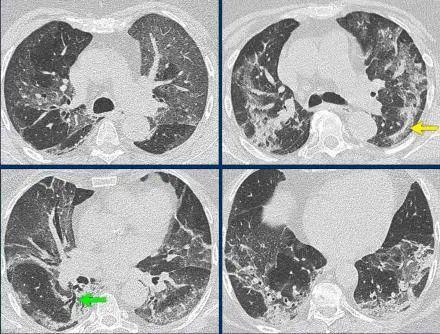

6、图片使用

虽然图片可以丰富文章的内容,但需要注意图片的使用应该与文章内容紧密相关,并且需要确保图片来源的合法性。